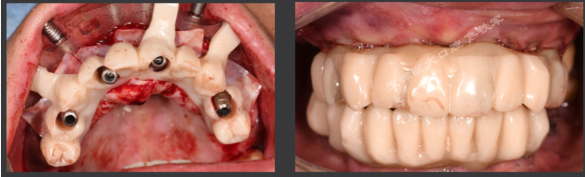

· 口内pick-up 固定临时修复体,患者上下颌咬合关系良好。

· 数字化设计第二幅临时修复体,PMM切削,上下颌各修复12个单位的修复体,16.26单端桥设计

· 第二幅临时修复体戴入口内,修复效果良好,前伸侧方咬合无干扰,预留清洁通道。

· 制作士卓曼原厂切削纯钛桥架+氧化锆整体桥+龈瓷。

· 修复体红白美学满意,前伸侧方咬合均无干扰,前牙前突问题解决,指导患者清洁。